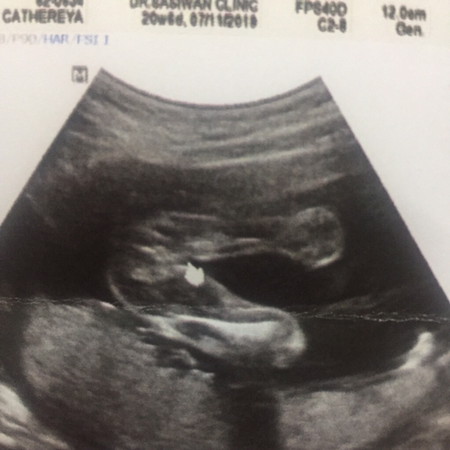

ซาวด์เมื่อ20w6d สอบถามไม่มั่นใจว่าญ รึ ช ค่ะ

ของแม่คนอื่นเห็นเป็นรูปขา ของเรานี่มองไม่รู้เรื่องเลย ใครมองออกบอกที แขนขาน้องอยู่ตรงไหน 55555

แบบนี้น่าจะผู้หญิงค่ะของเราเป็นผู้ชายใหญ่มากค่ะ

น่าจะหญิงนะคะ ถ้าชายจะยื่นออกมาเป็นแท่งๆนะคะ

ผู้หญิงค่ะ ถ้าผู้ชายจะมีปิกาจู้แล้วนะคะ

สาวน้อย ชัวส์ๆค่ะ เหมือนบ้านนี้เลย^^

น่าจะผู้หญิงค่ะ เป็นกลีบเลย

ผู้หญิงนะของบ้านนี้ปิกาจูโผล่เลย

หญิงคะชายจะยื่นออกมา